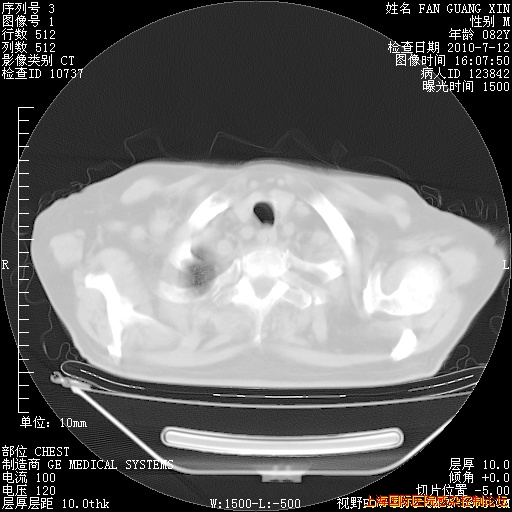

6月12日纵膈窗

整整相隔30天的肺部CT好像有所好转啊。甲强龙减量第3天,需要观察体温。

海管,自昨日你和我通完话后,不知您岳父消化道症状有无缓解?体温怎样?阅读7.12日胸部ct,个人认为目前激素治疗是有效的,甲强龙减量是适宜的。因在抗痨治疗,需密切观察肝功、肾功能和血常规。不过,老年、长期住院和大量使用激素,很担心菌群失调发生